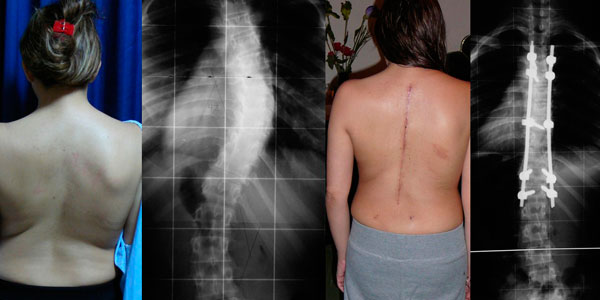

Mi mama y Yo comenzamos a notar que mi columna estaba torcida, consultamos varias clínicas y sinceramente el único que nos explico con detalle mi enfermedad fue el Dr. Carlos Cardenas, pareciera que otro médicos no conocían esta enfermedad. Mi diagnostico fue escoliosis idiopática del adolescente.

El único tratamiento para mi caso es con cirugía, tenia mucho miedo y me costo mucho decidir operarme.

Actualmente tengo 8 anos operada, y hago mi vida normal, hasta hago deporte, no tengo restricciones para nada.

Quería agradecer infinitamente al Dr. Carlos Cardenas, por el excelente resultado pero sobretodo por su profesionalismo.